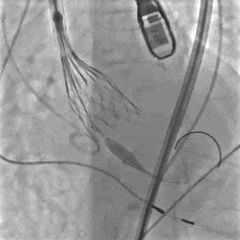

瓣膜按压后位置发生变化

多体位观察

瓣膜位于瓣上,选择回收

再次定位释放